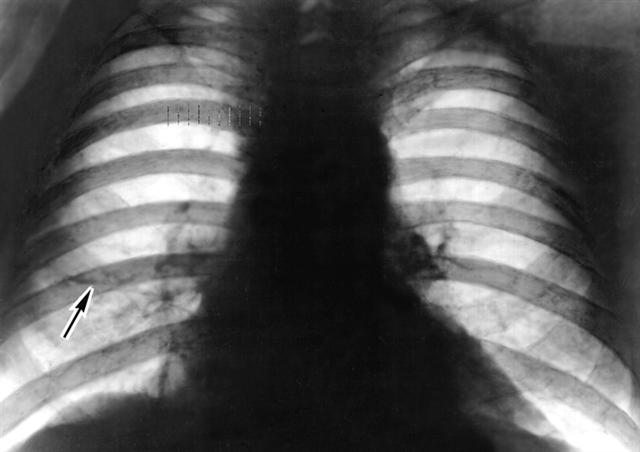

Рис. 4. Рентгенограмма грудной клетки (прямая прекция) больного саркоидозом легких: диффузное усиление и деформация легочного рисунка, дисковидный ателектаз (указан стрелкой).